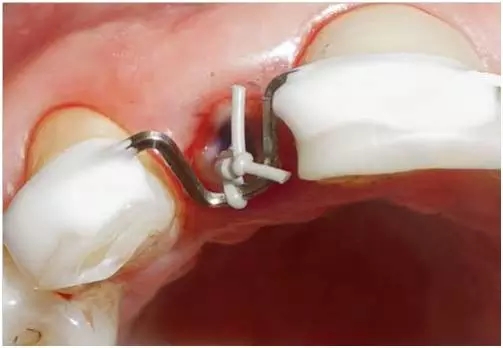

圖4:外傷9天后的臨床檢查:12牙牙冠在釉牙骨質(zhì)界水平處折斷。在使用牙齦收縮線后可以評估整個斷面。

圖12:12牙的臨床檢查:采用酸蝕粘接技術(shù), 用牙本質(zhì)粘合劑和Permaflow purple 在根管冠方段固定牽引環(huán)后的情況。

圖13:12牙的臨床檢查:開始正畸牽引牙根。牽引環(huán)被用彈性絞合絲固定在方弓絲上。